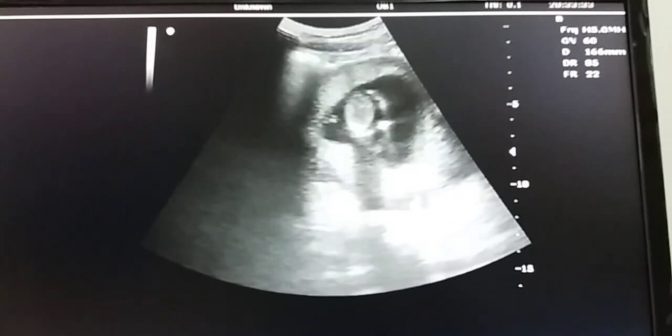

Ciri hamil 3 bulan bisa sangat menonjol dibandingkan saat awal kehamilan. Pada saat memasuki usia kehamilan 3 bulan, maka ibu akan mengalami berbagai gejala yang signifikan. Maka dari itu, ibu diharuskan selalu rajin konsultasi ke dokter kandungan untuk memastikan perkembangan kehamilan 3 bulan.